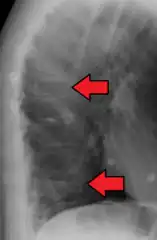

| Example of vertebral compression fracture. | |

A compression fracture is a collapse of a vertebra. It may be due to trauma or due to a weakening of the vertebra (compare with burst fracture). This weakening is seen in patients with osteoporosis or osteogenesis imperfecta, lytic lesions from metastatic or primary tumors,[1] or infection.[2] In healthy patients, it is most often seen in individuals suffering extreme vertical shocks, such as ejecting from an ejection seat. Seen in lateral views in plain x-ray films, compression fractures of the spine characteristically appear as wedge deformities, with greater loss of height anteriorly than posteriorly and intact pedicles in the anteroposterior view.[3]